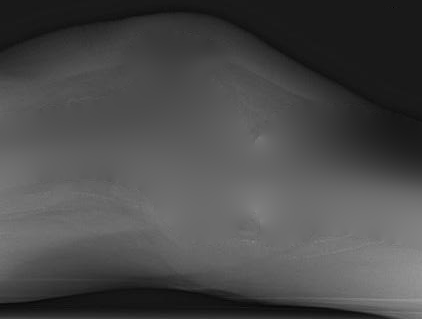

To tackle these problems, we propose to estimate the soft tissue image and bone image simultaneously without losing the linear relationship between image intensity and physical property of the imaging objects. Two examples from our method is shown in Fig. 1. The bone details are enhanced, which is theoretically guaranteed. The details of our method will be explained in later sections.

In later section, we will prove that (Eq. 8), which theoretically guarantees to increase the image contrast. This property becomes clear when we set the background . That is . It means , where is the standard gradient operator. Therefore, the contrast in bone image is theoretically larger than the contrast in the input image . This theoretical property is numerically confirmed by all our experiments.

One example is shown in Fig 5. And the middle line intensity profiles of original and our results are shown in Fig. 6. In this case, and the image contrast is enhanced. As shown in Eq. 8, and the enhancement is theoretically guaranteed. All our experiments also confirm this property.

Several results from our method are shown in Fig. 7. The left column is the original input image. The right two columns are the soft tissue and bone image, respectively. It can be told that the soft tissue image is smooth as we assumed. Meanwhile, the bone image has better image contrast as desired. Moreover, our method can reach real-time performance on these X-ray images. The running time of our method on these images is reported in Table I.